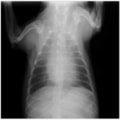

症例1:【マルチーズ 12歳齢 去勢オス】

A:胸部レントゲン写真 正面像

胸部レントゲン検査において重度の心拡大と肺水腫が認められた。超音波検査では、重度の僧帽弁閉鎖不全症、三尖弁閉鎖不全症、中程度の大動脈弁閉鎖不全症を合併していることが判明した。三尖弁逆流速度から肺高血圧症が示唆された。